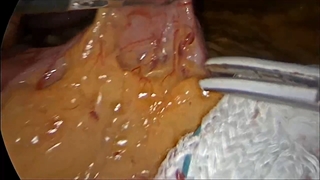

جراحی لاغری